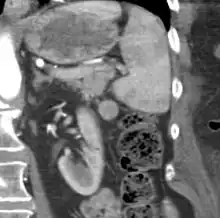

| CT scan of an accessory spleen (circular object in center of image) between the spleen and left kidney. | |

An accessory spleen is a small nodule of splenic tissue found apart from the main body of the spleen. Accessory spleens are found in approximately 10 percent of the population[1] and are typically around 1 centimetre in diameter. They may resemble a lymph node or a small spleen. They form either by the result of developmental anomalies or trauma.[2] They are medically significant in that they may result in interpretation errors in diagnostic imaging[2] or continued symptoms after therapeutic splenectomy.[1] Polysplenia is the presence of multiple accessory spleens rather than one normal spleen.

If splenectomy is performed for conditions in which blood cells are sequestered in the spleen, failure to remove accessory spleens may result in the failure of the condition to resolve.[1] During medical imaging, accessory spleens may be confused for enlarged lymph nodes or neoplastic growth in the tail of the pancreas,[5] gastrointestinal tract, adrenal glands or gonads.[2]